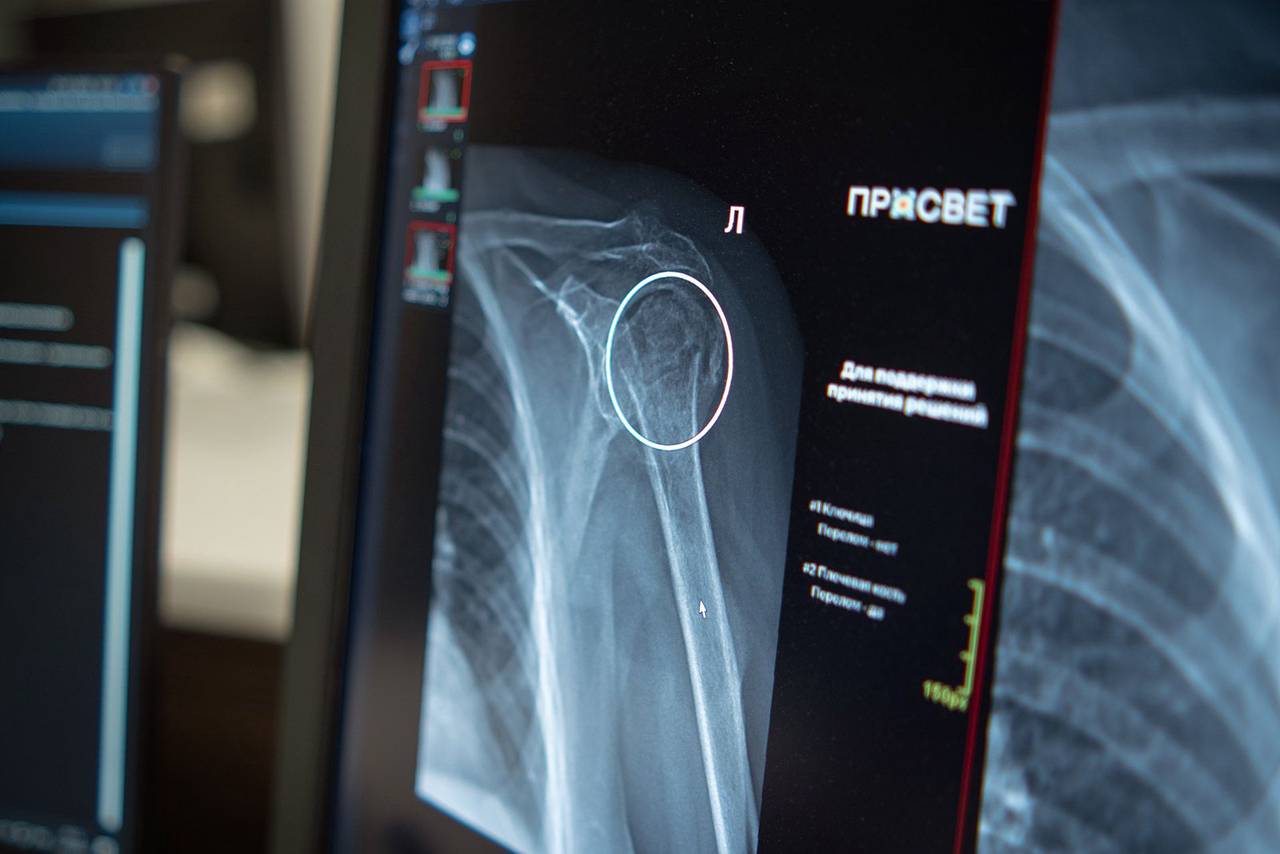

ИИ-сервис для диагностики переломов плеча появился в Москве

ИИ-сервис для диагностики переломов плеча появился в Москве. Фото: сайт мэра Москвы В столице начал функционировать новый сервис на базе искусственного интеллекта для обнаружения переломов […]